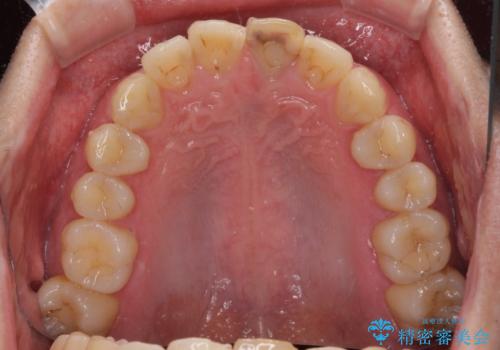

- 前歯が変色してしまったとのことで来院された患者様です。

変色が気になっていたものの痛みがなかったので看過していましたが、歯肉が腫れることが頻回となったため来院されました。

歯髄は既に壊死していたため、根管治療を行い、その後オールセラミッククラウンにて補綴することとしました。